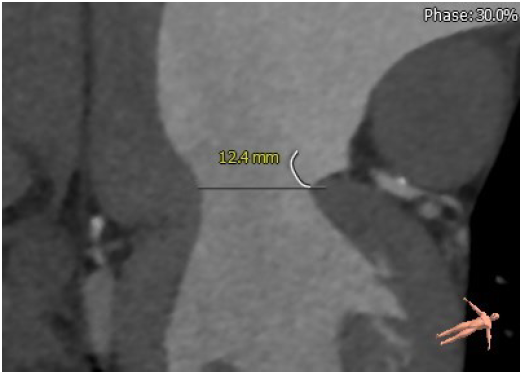

3. 患者左侧冠脉开口高度低LCA:3.1mm,左冠瓣瓣叶长度约12.4mm;右侧冠脉开口高度可RCA:16.8mm;

瓣叶长度:12.4mm